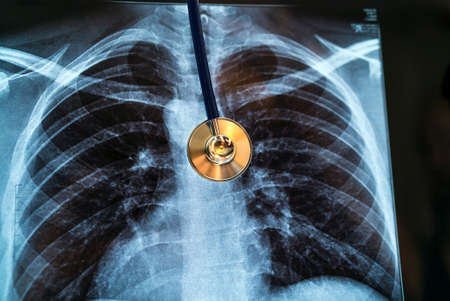

Chest X-ray image for physician's examination

Chest X-ray image for physician's examination